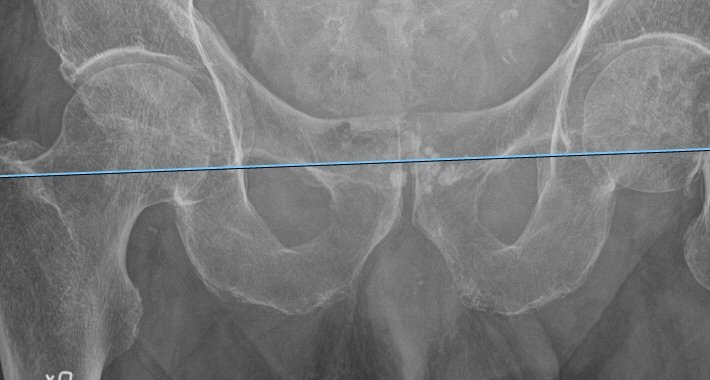

Referenslinje lagd med teardrops nedre kanter som referenspunkter

- Mät benlängdsskillnad som avstånd mellan trokanter majors övre spets alt. trokanter minors mitt, övre eller nedre begränsning och referenslinjen. Jämför höger och vänster sida.

- Notera att benlängdsuppskattningen påverkas av om bäckenet är tippat åt något håll, eller om endera femur står add- eller abducerat. Lägg därför referenslinjen även vid de andra referenspunkterna och försök analysera hur bäckentippning och/eller femurposition påverkar uppmätt benlängd.